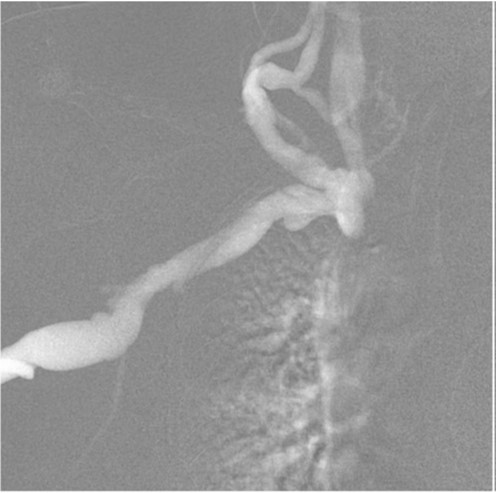

Fig. 1.

Fig 1. Venogram shows occlusion of the right brachiocephalic vein with multiple collaterals in the right neck.

우측 중심정맥조영술에서 우측 상완두정맥(brachiocephalic vein)이 완전히 막혀있고 경정맥으로 여러 개의 측부혈관(collateral vessel)들이 관찰됨

초음파 유도 하에 우측 팔의 동정맥루 graft를 천자한 후 정맥조영술을 시행하여 우측 상완두정맥의 폐색을 확인함(Fig. 1). 5Fr Cobra 카테터(Cook, Bloomington, IN, USA)와 친수성 0.035 inch 유도철사(Terumo, Tokyo, Japan)로 폐색부위의 통과를 시도하였으나 실패함. 우측 대퇴정맥을 천자하고9Fr 65cm sheath (Arrow, Deutschland, Erding, Germany)를 상대정맥까지 진입시킨 후 5Fr Davis 카테터를 통해 약 2cm 길이의 상완두정맥 폐색 부위를 확인함(Fig. 2). Davis 카테터와유도철사로 상대정맥에서 우측 상완두정맥으로 통과를 시도함. 유도철사의 soft tip 부분으로 시도하였을 때 통과가 되지 않아서 반대쪽 hard tip 부분으로도 통과를 시도 하였으나 실패함(Fig.3). 유도 철사의 soft tip 과 hard tip 양쪽 모두 사용 하여 통과를 시도하였으나 막힌 부위의 위쪽 부분은 앞쪽(anterior side of the body) 을 향하고 있고 아래쪽 부분은 뒤쪽(posterior side of the body)를 향하고 있어서 천자 방향을 맞추기 어려웠음(Fig. 3). 우측 내경정맥을 천자하고 5Fr sheath를 삽입함. Sheath를 통해서 5FrKumpe 카테터와 0.035 inch 유도철사로 위에서 아래 방향으로 폐색부위 통과를 시도함. Hard tip으로 시술 도중 폐색혈관 주위로 유도 철사가 천자되어서 조영제의 누출이 있었으나 천자부위 주에 국한되어 있었고 임상적으로 문제 있는 혈류역학적 변화는 오지 않았음. Kumpe 카테터와 유도철사로는 천자 방향을 맞추기가 어려워서TIPS set (Cook, Bjaeverskov, Denmark)를 사용하기로 함. 천자된내 경정맥에 10Fr introducer sheath를 삽입하고 20G Colapinto needle을 폐색부위까지 진입시킴. 양쪽에서 정맥 조영술을 시행하여 폐색된 부위의 위치와 길이를 여러 각도에서 정확히 파악한 후, 폐색 부위를 천자함(Fig. 4). 천자 후 Colapinto needle을 통해 유도철사를 상대정맥에 진입시킴. 대퇴동맥을 통하여 삽입된 snare 카테터(ev3, Plymouth, MA, USA)를 이용하여 대퇴정맥 밖으로 유도철사를 빼냄(through and through technique)(Fig 5). 유도 철사만 통과된 상태에서 천자부 주위에 여러번의 천자로 인한 조영제 누출이 있었으나 주출된 조영제의 양이 적었으며 천자부 주위에 국한되어 있었음. Tractogram시행시 조영제의 누출은 보이지 않아서 유도 철사 주위에 국한 되어 있어서 풍선확장술을 시행 하기로 함(Fig. 6).대퇴 정맥을 통해 유도철사를 0.035 inch Amplatz wire(Cook, Bjaeverskov, Denmark)로 교체하여 내경정맥까지 진입시킨 후 풍선카테터 (Bard, NJ, US)를 삽입함.천자된 통로를 따라 직경 6 mm에서부터 16 mm까지의 풍선카테터로 차례대로 풍선확장술을 시행함(Fig. 7). 시술 후 정맥조영술에서 폐색부위는 개통되어 원활한 혈류를 보였음(Fig. 8). 시술 후에 오른쪽 팔의 종창은 호전됨.